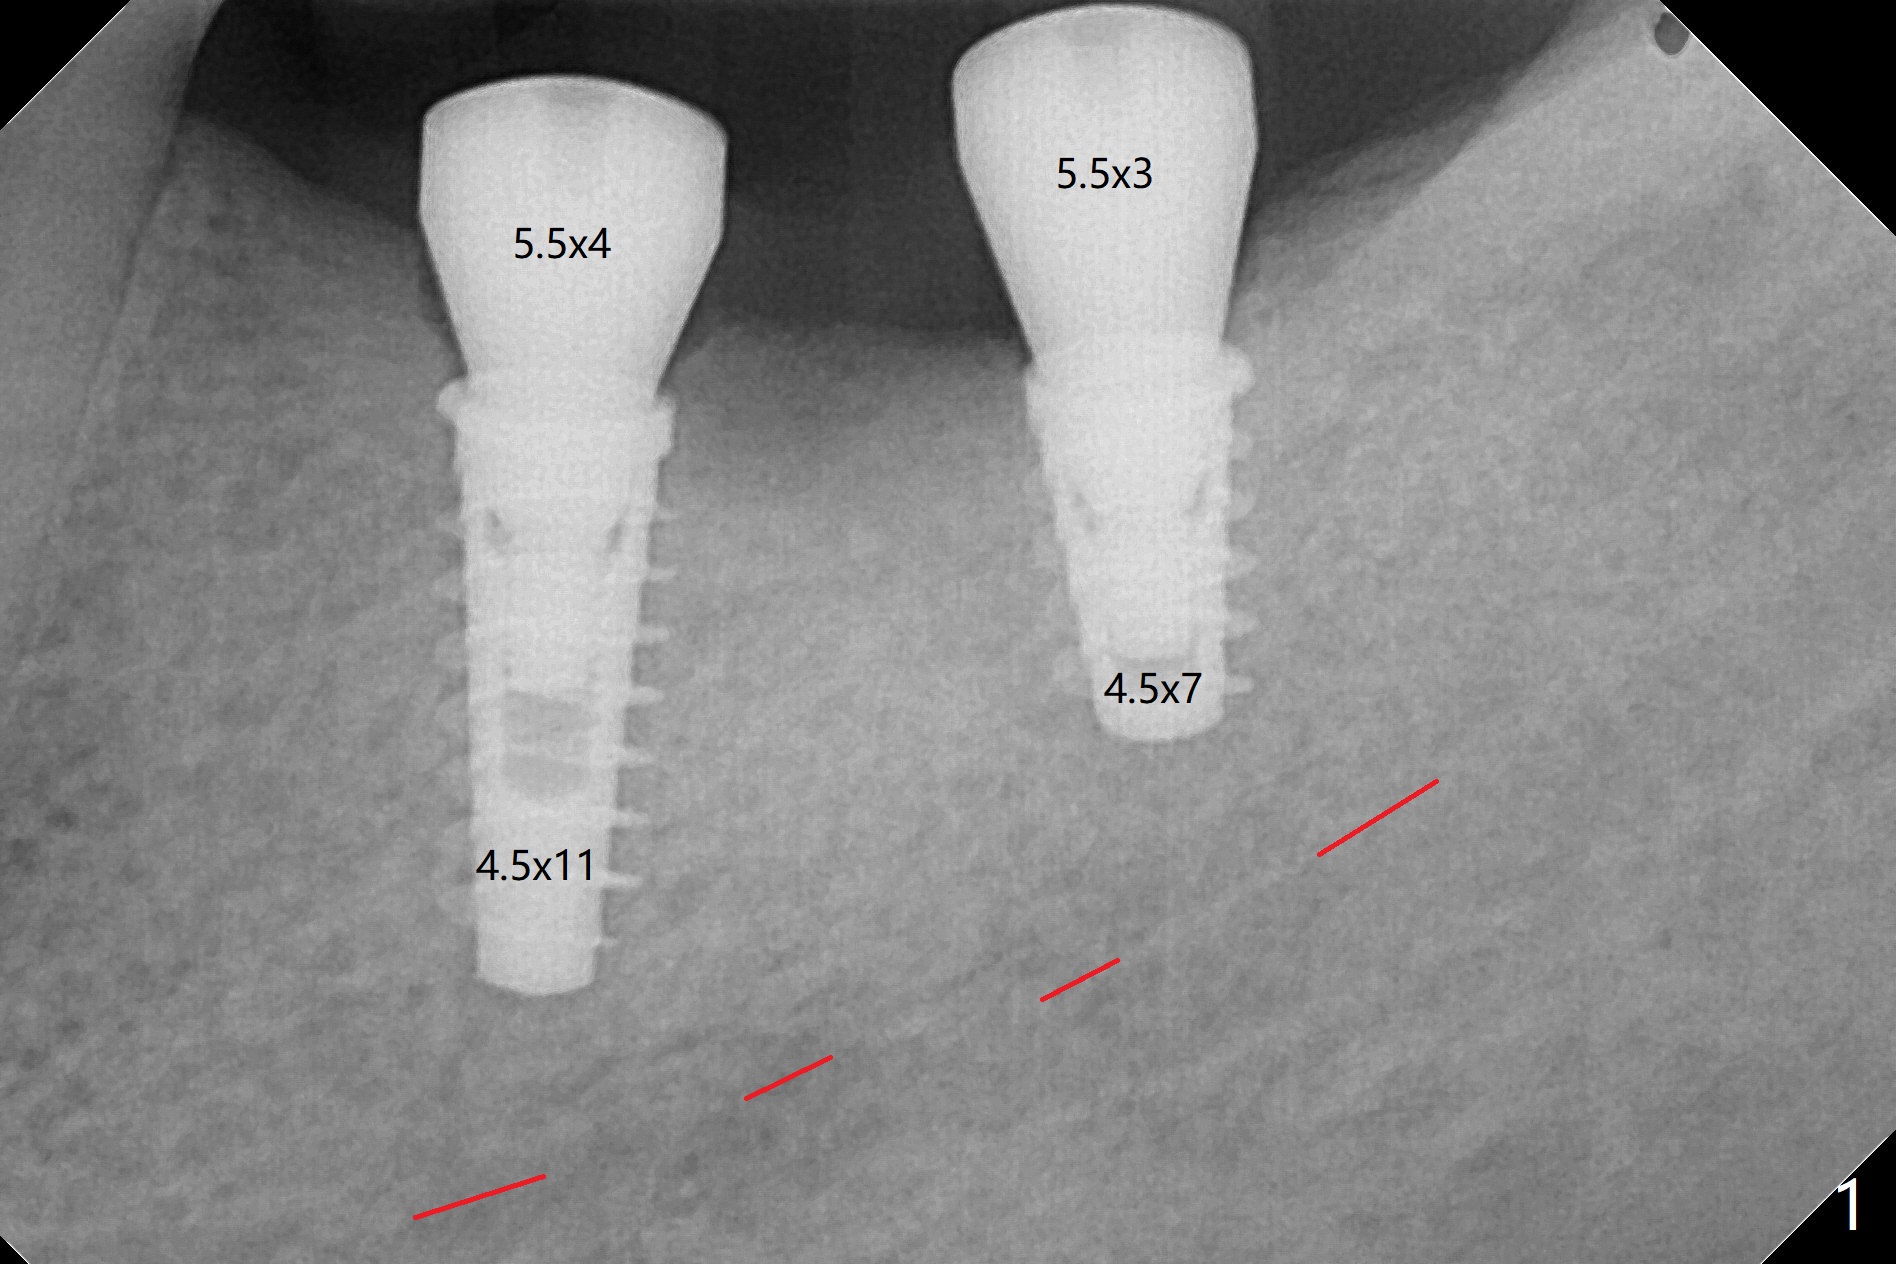

Following placement of a 4.5x11 mm implant at #19 (14 months post guide fabrication), a fixture anchor pin is placed. With stable guide, it is much easier to finish osteotomy and implant placement at #18 (Fig.1). Since the patient is nervous and sensitive to drilling, a shorter implant is placed (7 mm instead of 9 mm vs. 8.5 mm drill). The stability is unaffected because of the dense bone. After use of 5.5 mm profile drill, healing abutments (5.5x3 and 5.5x4 mm) are placed without interference. There is crestal bone loss in 3 months (Fig.2, as compared to Fig.1). Since there is more space apical to the pair abutment at #19 than that at #18, incomplete abutment seating is suspected at #19. More X-ray will be taken (Fig.3,4). In fact, it is not necessary. The space differential is also noted with healing abutments in Fig.1. BW cannot tell whether the abutment at #19 is seated or not (Fig.3). When the abutment is changed at #19 with 30 Ncm torque, the space differential remains (Fig.4, as compared Fig.2) and must be normal. The shorter implant at #18 appears not osteointegrate, since the patient feels pain when the abutment is torqued at 15 Ncm. The patient returns for temporary crown contour adjustment 1-2 weeks later. The implant at #18 is removed when the abutment screw is untightened 7 months postop; Cortical bone is placed with 6 month membrane (Fig.5). Three months later, incision will be made with reuse of the guide with fixture pin at #19. If a 4.5x9 mm implant cannot be placed, bury a short and/or narrow implant. Impression will be taken for #19 soon. In fact fixture pin cannot be seated. It appears that cancellous bone reforms, presumably low density. Underdrilling is conducted in diameter. The torque is high, but normal drilling is not carried out. The former implant exfoliated probably due to compression necrosis. The new implant is not completely seated, partially out of fear of being close to the Inferior Alveolar Canal (Fig.6). After cortical plate perforation, allograft is placed (Fig.7 *), followed by buccal flap release (periosteum underscored). In fact the implant does not have enough clearance from the Canal (red dashed line: the superior border of the Canal). The abutment at #19 returns to hold periodontal dressing in place. The implant is buried in the bone except lingual 4 months postop (Fig.8,9).